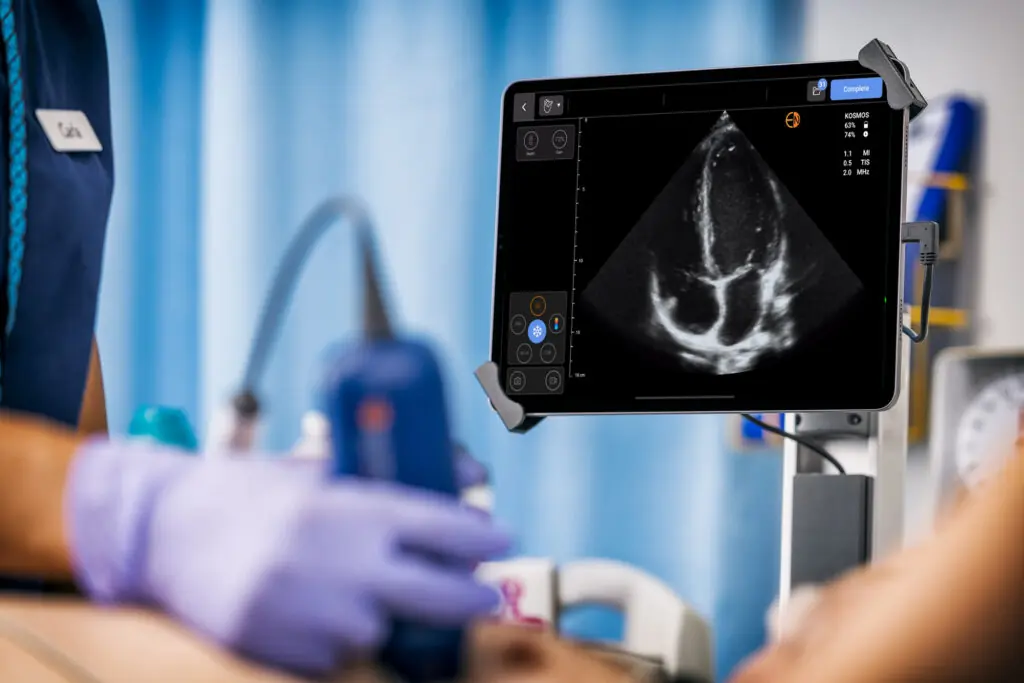

Kosmos Plus, a state-of-the-art portable ultrasound, offers an innovative solution by providing comprehensive echocardiography capabilities at a fraction of the cost of traditional echo machines or portable echo machines.

Kosmos Plus is a compact, portable, AI-driven ultrasound solution that provides high-resolution cardiovascular imaging, making it a game-changer for cardiology clinics. It combines portability with advanced functionality, offering a cost-effective alternative to traditional ultrasound machines and helps enhance clinical decision-making and patient outcomes [6].

Kosmos Plus delivers crystal-clear images that rival traditional echocardiography machines, thanks to its gold-standard PZT crystal transducer and advanced capabilities [Advanced Doppler features like PW, CW, TDI, & more with cardiac probe].

Kosmos Plus is a highly portable ultrasound machine that functions as a portable echocardiogram machine, allowing cardiologists to perform high-quality imaging at the bedside or in the clinic.